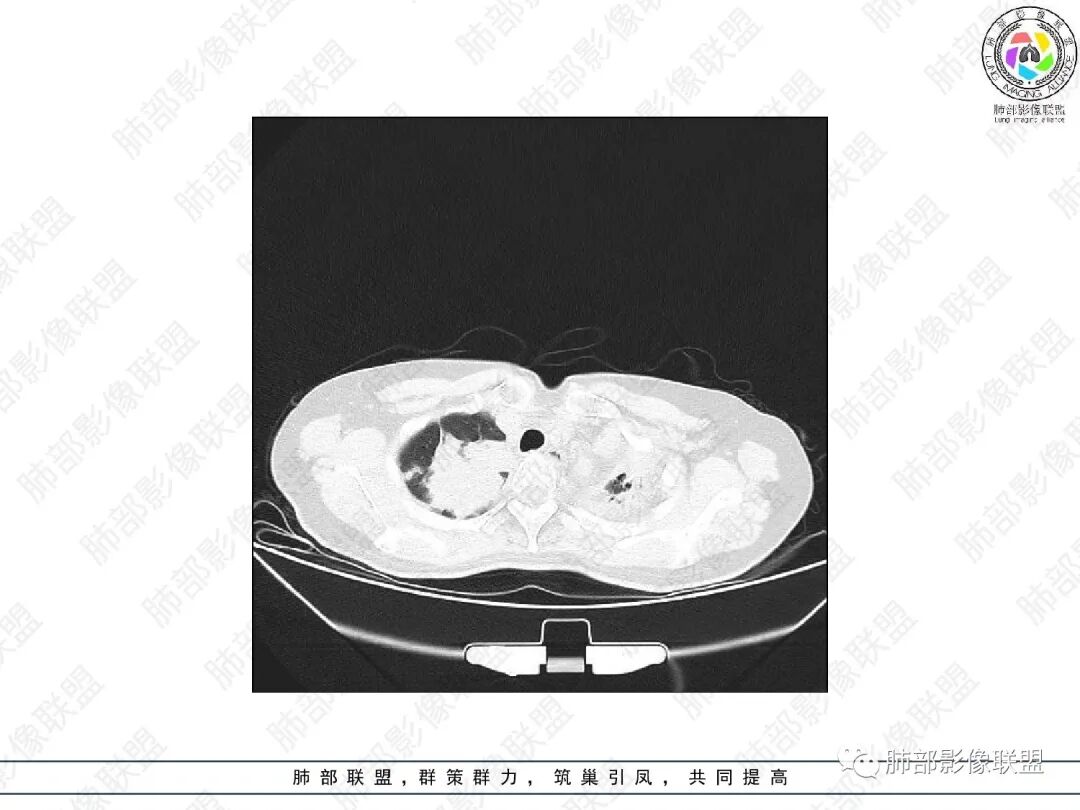

1.中年女性,主因“咳嗽、咳痰半年余”入院,既往史:8年前因左肺病在外院变行左肺叶切除术,诉术后抗结核治疗1年,具体病理等不详。实验室IGE显著增高。

2.胸部CT:右肺上叶及中叶不规则块状影,沿支气管走行方向指套样影,支气阻塞湖嵌塞,腔内可见高密度影。灶周可见磨玻璃,外围见结节影及树芽征。左肺体积缩小,见不规则条索影、胸膜增厚,纵隔牵拉左移。

3.综合分析:结合患者病史及胸部CT主要鉴别ABPA(右肺上叶不规则块影,指套样顺延支气管方向,抗结核治疗1年,肺部病灶仍明显)及继发性肺结核TB(右肺上叶不规则肿块,其可见高密影,边缘模糊,周围卫星灶、树芽征,沿支气管爬行)。

完善气管镜及病理、检验结果(IgE显著增高)等支持ABPA诊断。且给予激素及伊曲康唑治疗后复查胸部CT提示病灶较前吸收,所以诊断明确。